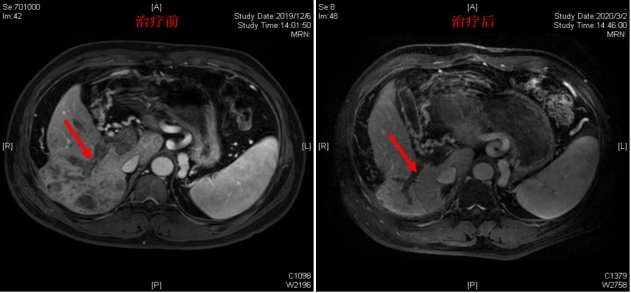

肝癌,肺癌,肠癌等肿瘤的综合治疗,尤其是在肝癌治疗方面,采用放射治疗+靶向药物+免疫药物联合治疗。运用现代放疗技术突破了过去认为肝癌放疗不敏感的禁区,并自创“二药联合”、“三药联合”,使大多数不能手术的患者得到了有效治疗。